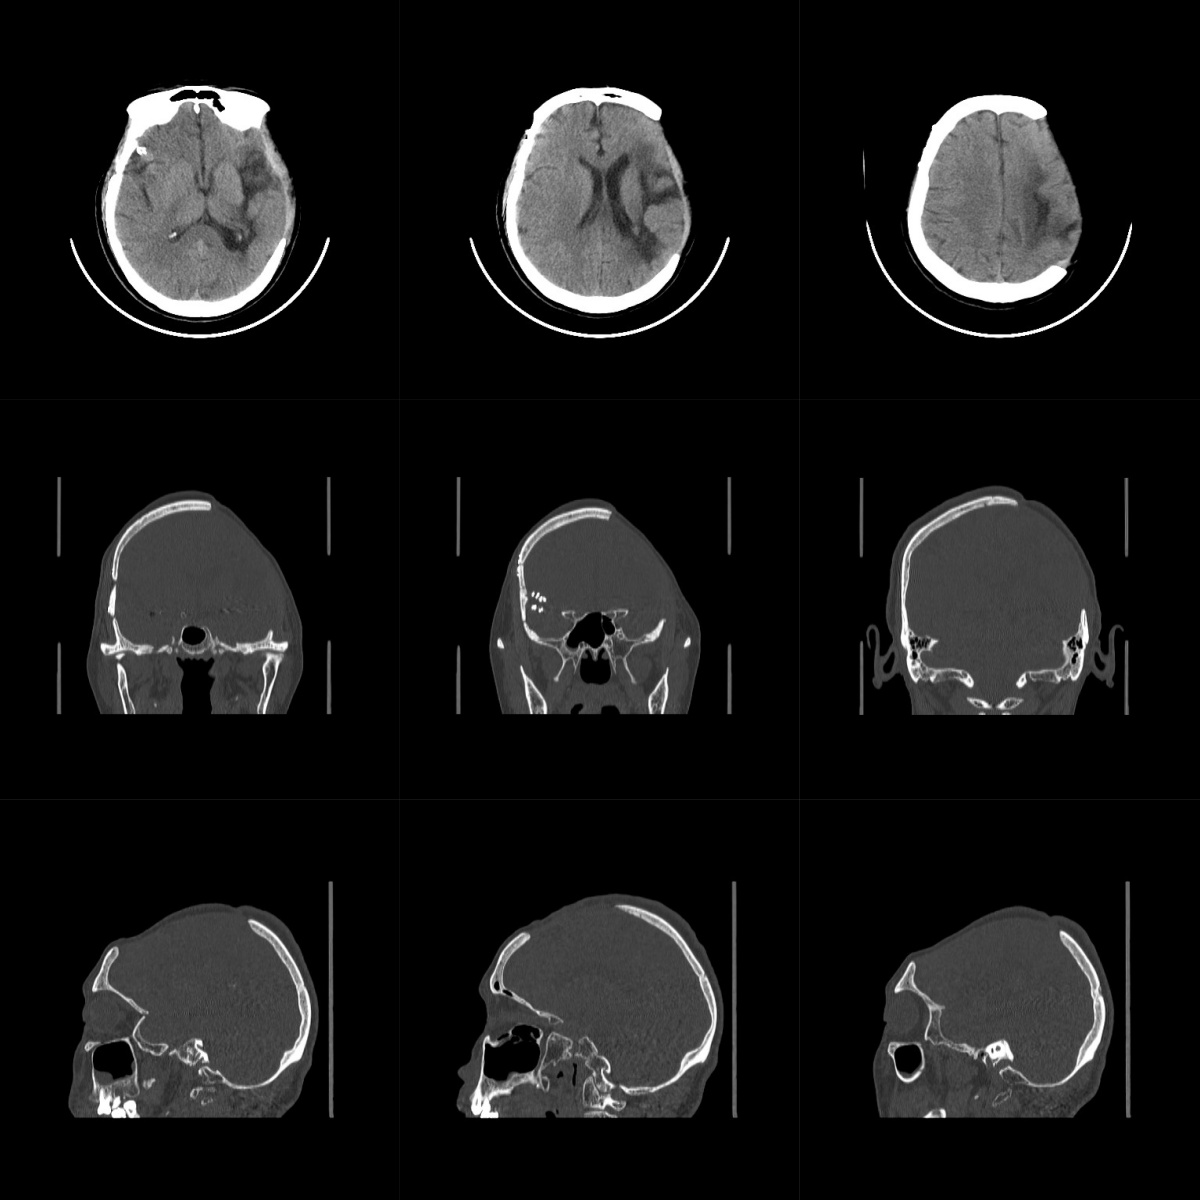

2024年3月1日患者晨起后突發頭暈,繼而意識不清,急被送至當地醫院就診,行頭顱CT檢查,結果顯示:“左側基底節區腦出血”。急診手術治療,行開顱血腫清除、去骨瓣減壓術,術后患者逐漸清醒,遺留失語,右側肢體偏癱。后續行肢體功能鍛煉、針灸、高壓氧等康復治療。

為進一步診治并行顱骨缺損修補,患者于2024年5月14日以“顱骨缺損、腦出血術后恢復期、高血壓”入院聯勤保障部隊第九八〇醫院神經外科。患者既往2003年診斷為“煙霧病”,未行特殊治療。2017年因右側大腦中動脈瘤于外院行介入治療。

患者mRS評分4分,GCS評分13分(E/V/M=4/3/6)。神志清楚,失語,左側額顳頂部可見長約27cm問號形切口瘢痕,顱骨缺損范圍約10×12cm,骨窗張力不高,可見腦搏動。雙側瞳孔等大等圓,直徑2.5mm,對光反射靈敏。